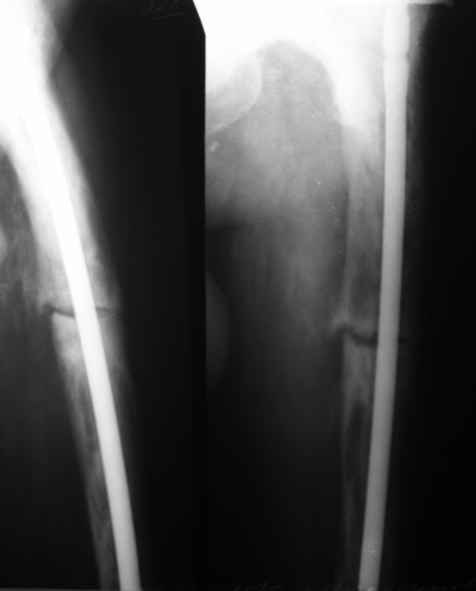

Re: перелом бедра на фоне болезни Педжета

Пациент 82 лет, поступил через 5 мес. с несросшимся переломом после открытого интрамедуллярного остеосинтеза. Выполнили реостеосинтез стержнем 12 мм. ( мах. доступного нам в 2003 г.) Через 4 мес динамизация. В течении 2х лет сращения нет, тем не менее конечность опорна (ходит с тростью). От очередного реостеосинтеза отказались из-за сопутств. патологии.